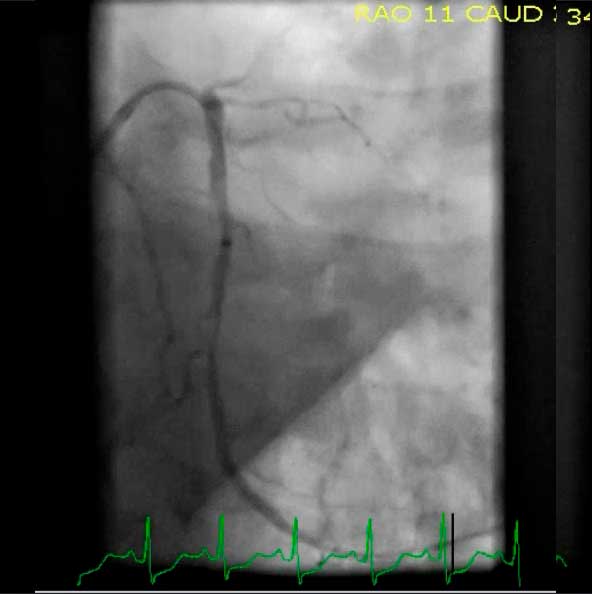

А что если эквифазный комплекс QRS виден в отведении aVF? Например, как в этом случае:

Эквифазный QRS aVF у больного с тампонадой сердца

В этом случае - все крайне просто! Вы можете быть уверенны, что электрическая ось сердца направлена в сторону отведения I, т.е. имеет угол 0°. Обратите внимание, что при такой ЭОС в отведении I должен быть максимальный положительный комплекс QRS.